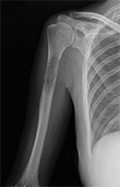

La localización de la Metástasis Ósea se produce frecuentemente en el esqueleto axial, (raquis y pelvis). Aun así, también se encuentran en la metáfisis proximal de huesos largos y en las extremidades (relacionado con un cáncer primario pulmonar o tiroides). En raras ocasiones aparece por debajo de codo o de rodilla.

- Entre un 10 y un 30% de los pacientes que padecen Metástasis Ósea sufrirán una fractura de hueso largo que prescindirá tratamiento quirúrgico.